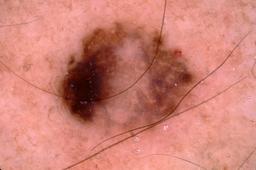

{

"age_approx": 40,

"anatom_site_general": "lower extremity",

"concomitant_biopsy": true,

"dermoscopic_type": "contact non-polarized",

"diagnosis_1": "Benign",

"diagnosis_2": "Collision - Only benign proliferations",

"diagnosis_confirm_type": "histopathology",

"image_type": "dermoscopic",

"lesion_id": "IL_8263283",

"patient_id": "IP_8318198",

"sex": "male"